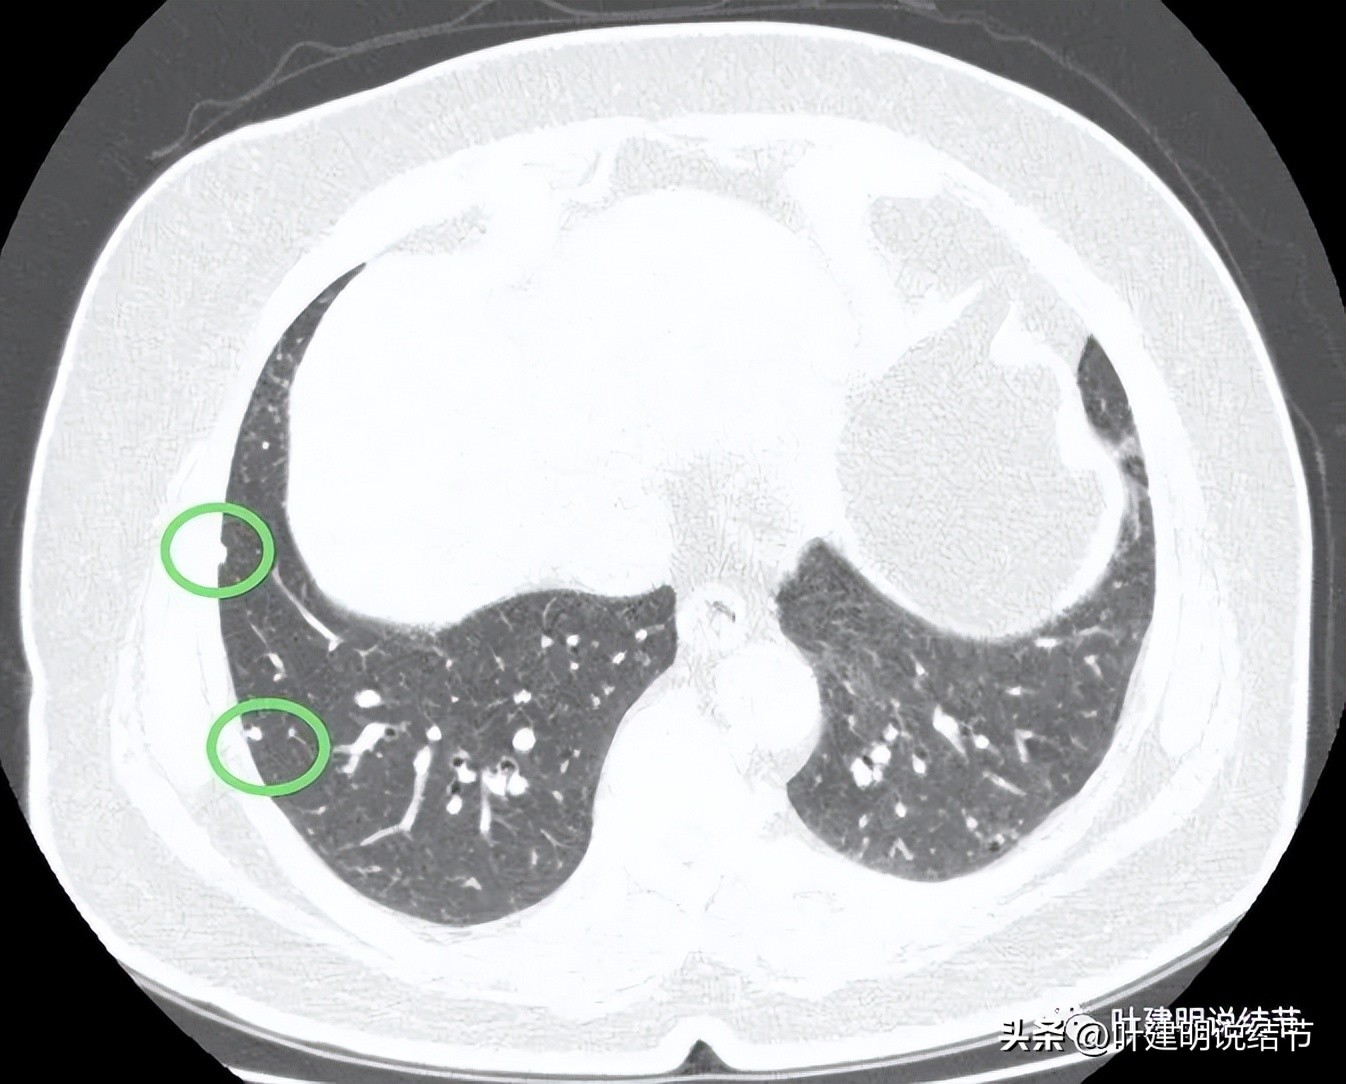

病灶1:右上叶实性小结节,密度高,胸膜下,考虑良性可能性大

病灶2:右中叶微小实性结节,考虑纤维增生结节可能性大